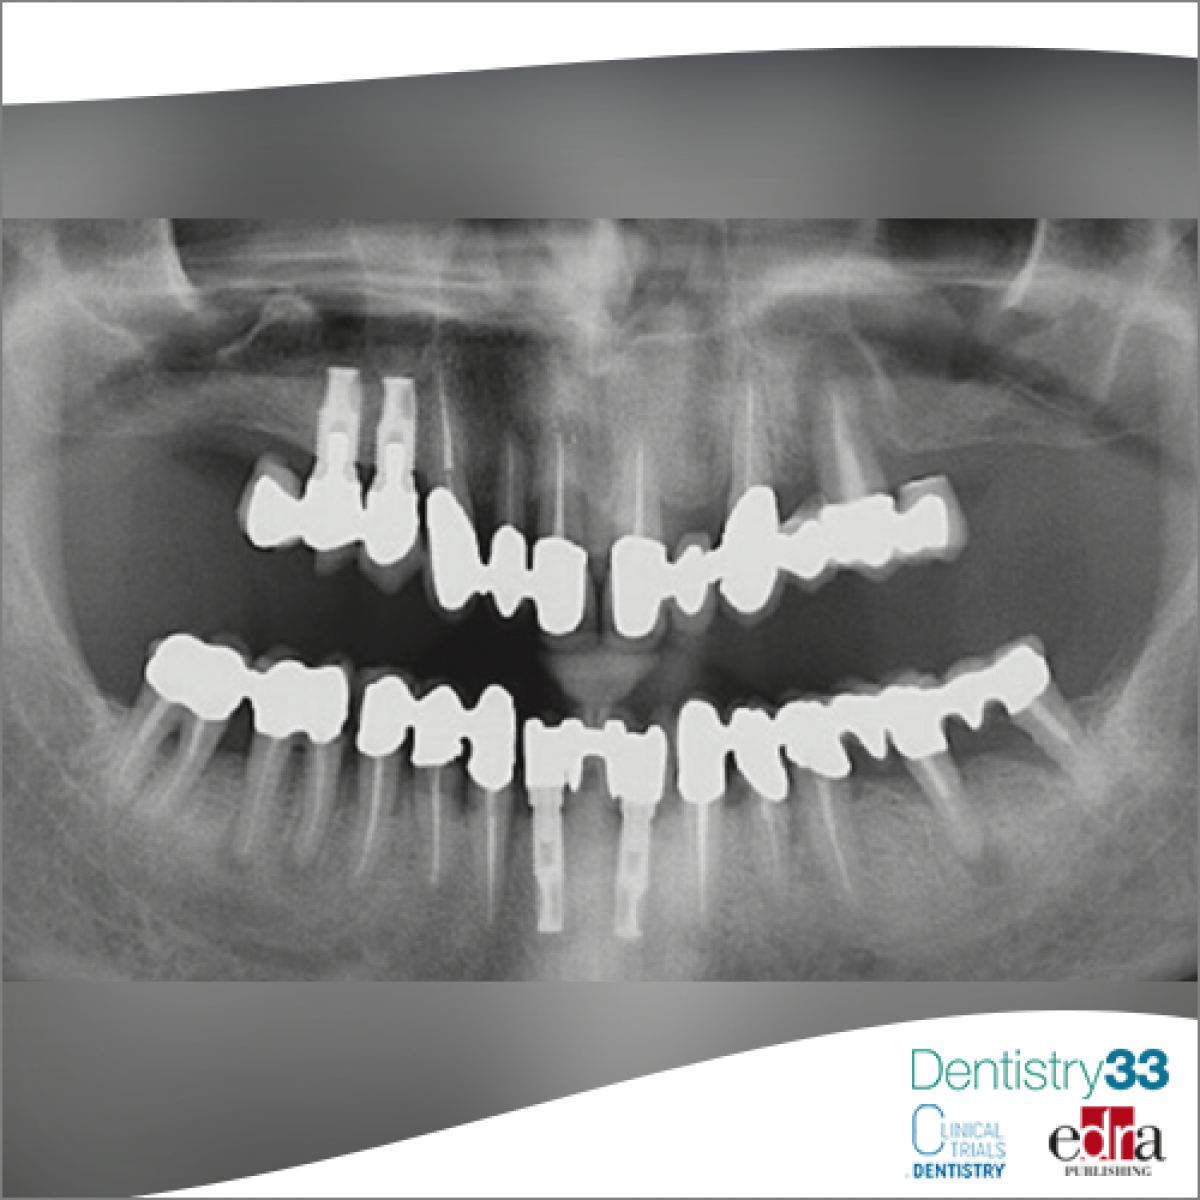

A 76-year-old male patient was sent to the oral medicine service of the San Paolo Hospital in Milan for the presence of a radiolucent lesion at the level of the left mandibular corner, found through orthopantomography. (fig 1)

On CBCT examination, a radiolucent lesion of about 2 cm of major axis is highlighted, with blurred margins at the level of the left mandibular corner.